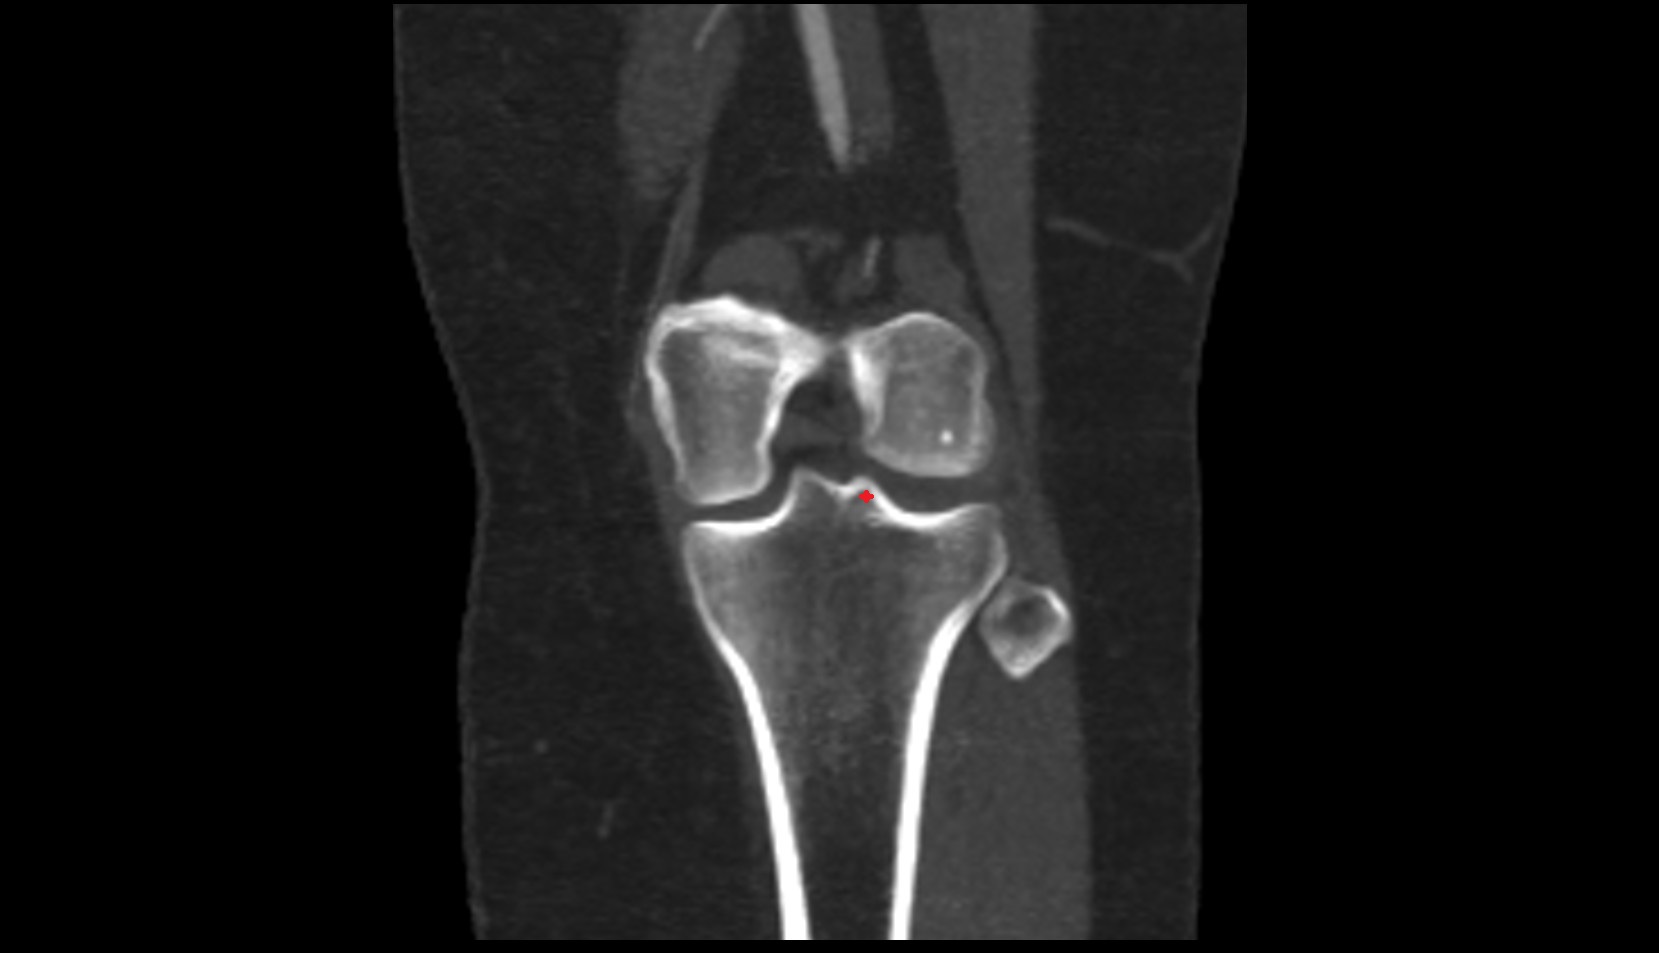

- Knee Joint